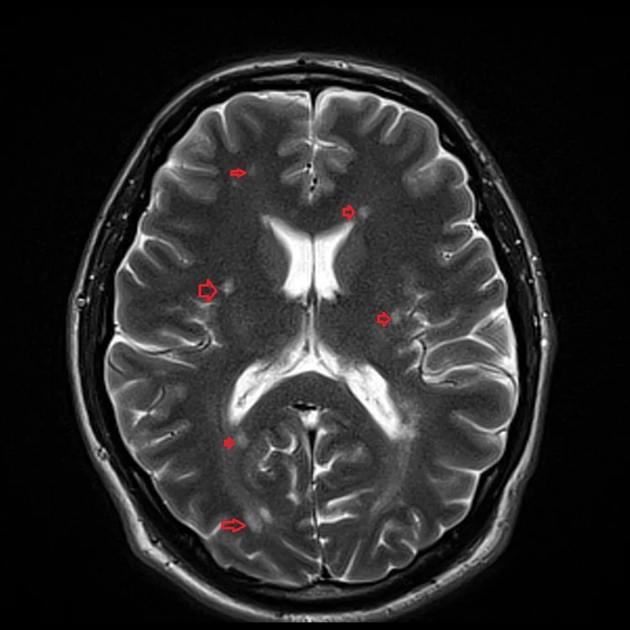

A “Brain with MS Protocol” is a specialized imaging approach designed to assess the brain for signs of multiple sclerosis (MS), a chronic autoimmune disorder that affects the central nervous system. This protocol typically involves high-resolution magnetic resonance imaging (MRI) using specific sequences such as T2-weighted, FLAIR (Fluid Attenuated Inversion Recovery), and post-contrast T1-weighted imaging. The goal is to identify and evaluate lesions or plaques in the brain’s white matter, which are characteristic of MS. FLAIR sequences are particularly useful for detecting periventricular and cortical lesions, while contrast-enhanced MRI highlights active areas of inflammation. The protocol also includes evaluating the size, location, and number of lesions to help diagnose MS, assess disease progression, and monitor the effectiveness of treatment. MRI is essential in distinguishing MS from other neurological conditions and plays a key role in managing the disease over time.

Brain with MS protocol (Multiple Sclerosis) (MRI)